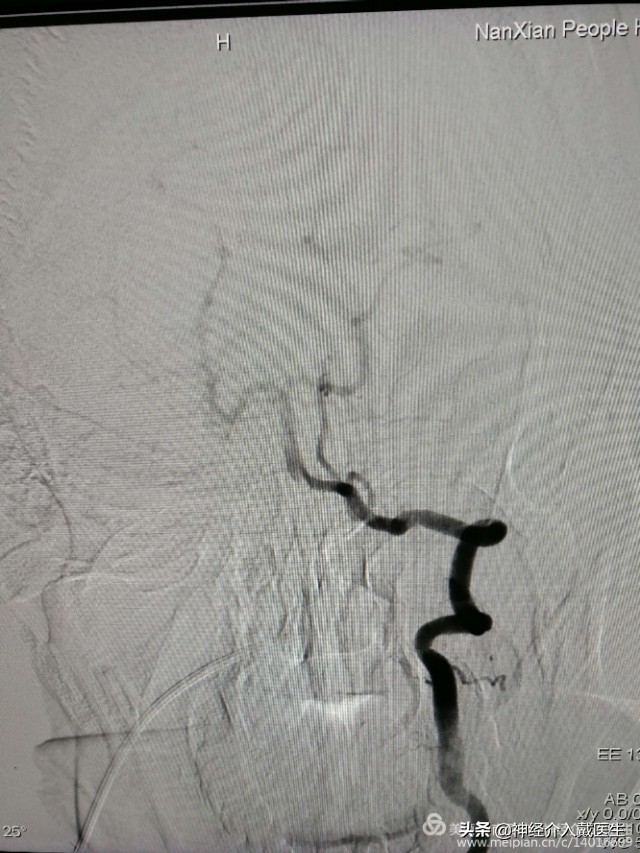

脑血管造影显示右侧椎动脉V4段动脉瘤,并且是比较少见的夹层动脉瘤。长度大约9mm,动脉瘤破口与右侧椎动脉重要分支右侧小脑后下动脉很近。

动脉瘤手术经典治疗方式有开颅夹闭术和介入栓塞术,该动脉瘤位于后循环,后颅窝,脑干附近,显露困难,并且是夹层动脉瘤,开颅夹闭术不合适,介入栓塞术是最好的选择,该动脉瘤位于椎动脉重要分支右侧小脑后下动脉开口处,所以保护右侧小脑后下动脉是手术的重中之重。仔细观看3D,动脉瘤破口与右侧小脑后下动脉开口还是有一定的距离,又是破裂动脉瘤,支架加弹簧圈栓塞是最好的选择,必要时可以用微导管或者支架保护右侧小脑后下动脉。